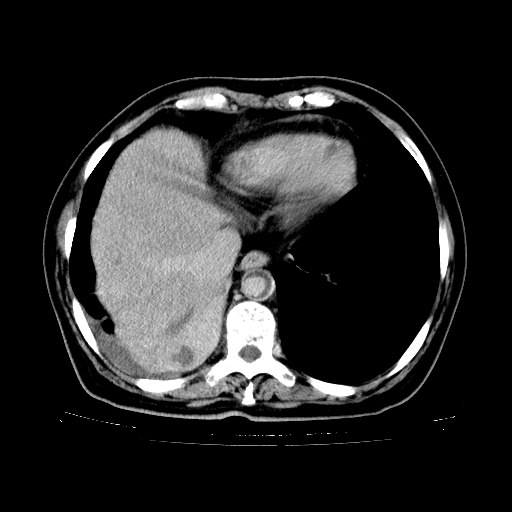

2.胸主动脉夹层。

支持,首先一元论解释。胸主动脉部分层面环形低密度,中心强化。环形影不强化。不象真假腔的改变。我考虑动脉炎,不太支持夹层动脉瘤-和大家的观点不一致,希望楼主让患者再做个心血管的彩超吧。

继发型肺结核,右下肺支气管内膜结核.右侧少量胸腔积液.主动脉夹层.